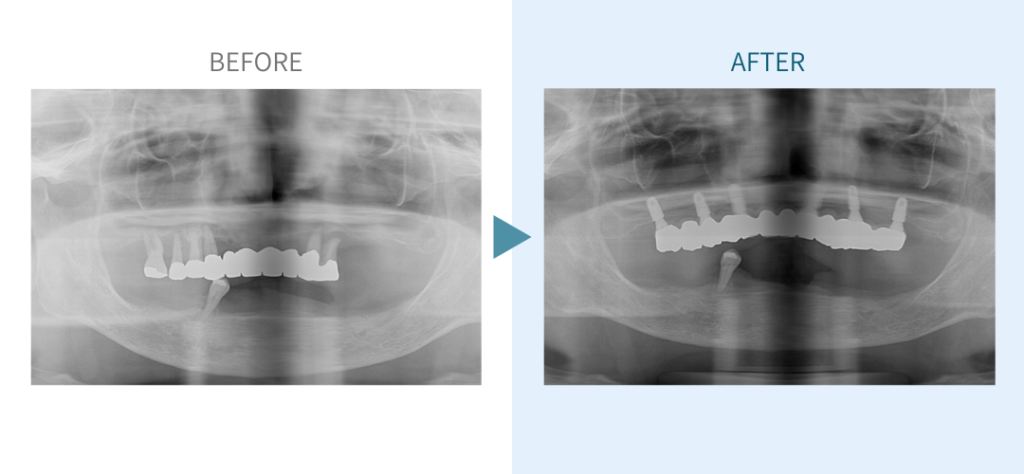

デンタルチームジャパンでは、サイナスリフト(上顎洞底挙上術)や骨造成など、他院で「骨が足りない」と断られた難症例にも対応しています。

こうしたケースは一般的に大学病院以外では難しく、大学で治療を受ける場合は費用が当院の倍以上になることもあります。

私たちは、難症例に関する治療法を学会でも発表しており、その豊富な実績と技術力が評価され、全国から患者様が来院いただいております。

こちらではその一部の症例についてご紹介します。